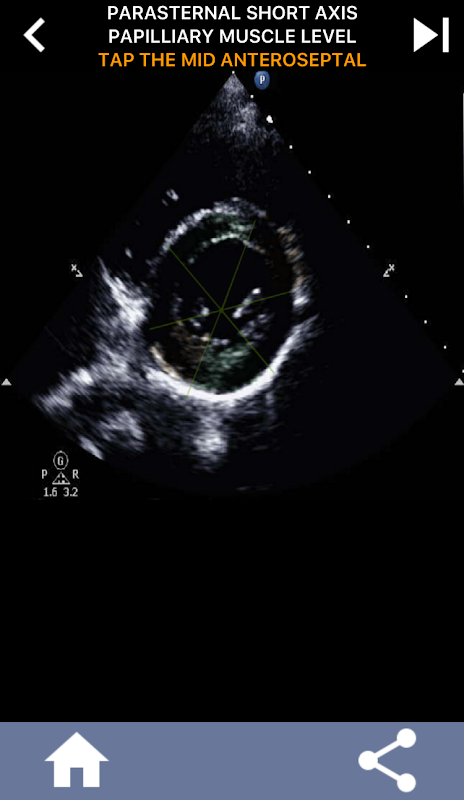

Approccio visivo basato su quiz per l'apprendimento dei segmenti cardiaci AHA: ecocardiografia

Questa app metterà alla prova le tue conoscenze utilizzando immagini eco reali, che spesso trovo essere il miglior metodo di insegnamento.